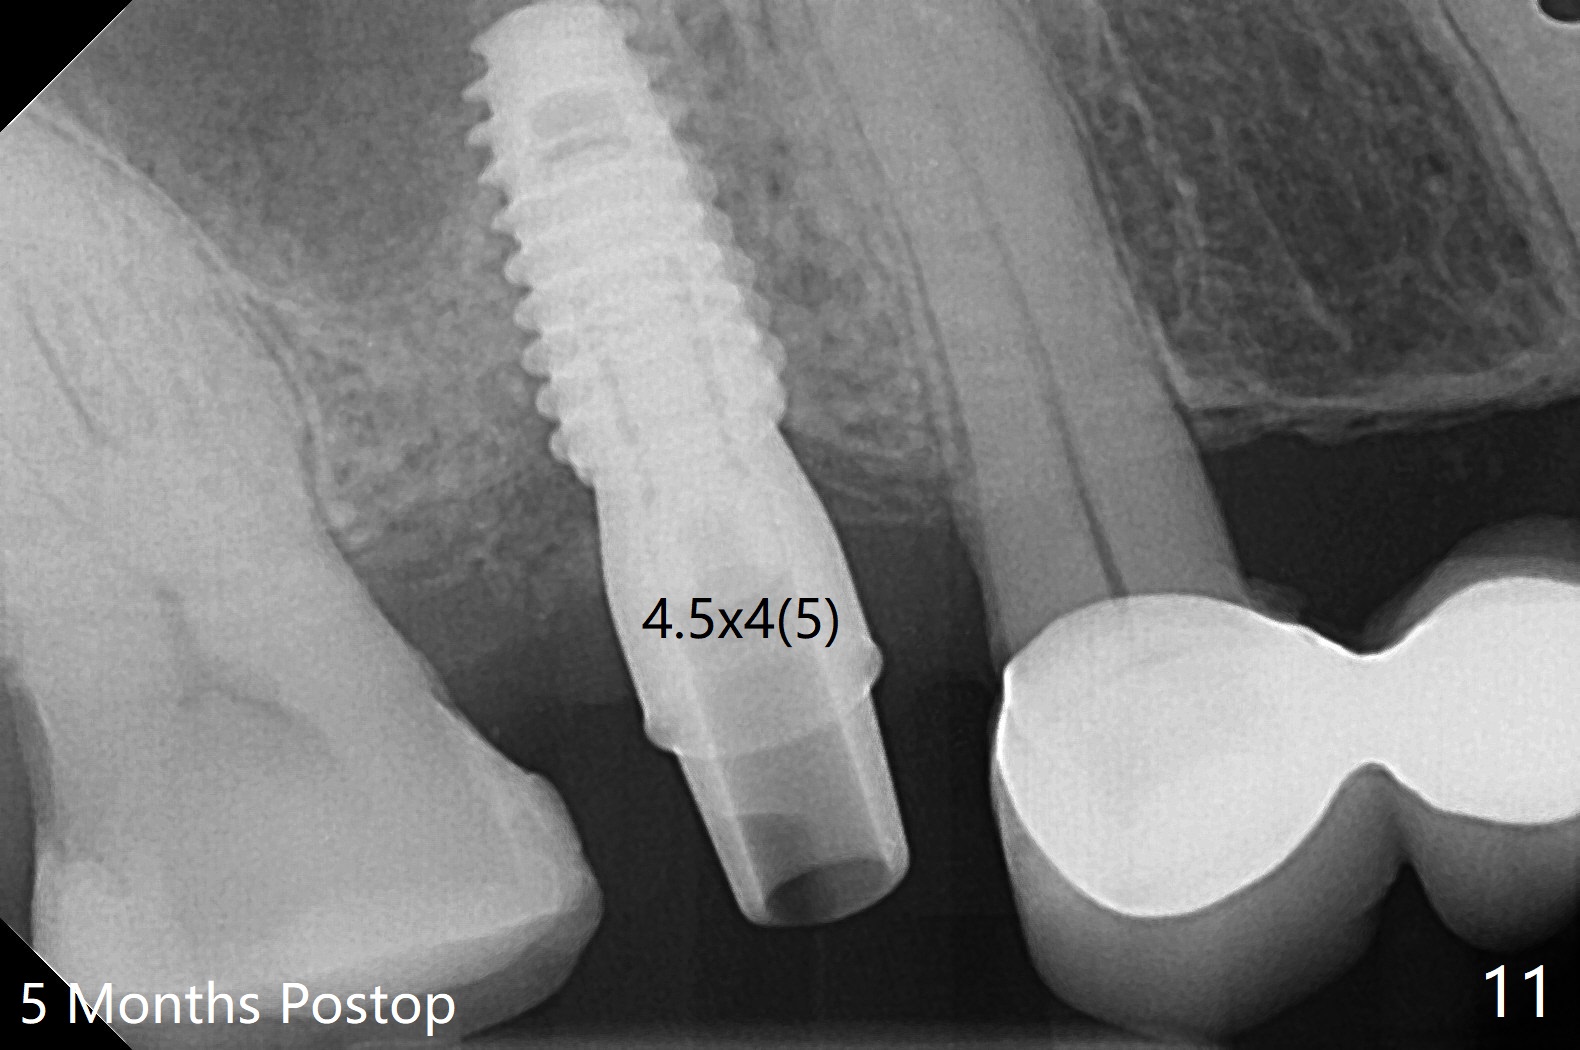

提取上清液后,红管再次离心,同样速度,5分钟,便形成PRF(胶状,上面黄色部分,图七),由于试管在离心机放置角度缘故,PRF与下面红血球部分(深色)交界处是一个斜面,制作PRF膜前,必须在交界处下面剪(图八白斜线),因为在交界处有效成分浓度最高,请看录像(虽然剪的太高些)。制作完毕的PRF膜可以覆盖图四骨块表面,但是用于图一之后,塞入上颌窦(录像),目的促进上颌窦膜修复,万一提升时出现隐形破裂。术后五个月放置5.5x4(4)毫米基台,未完全就位:基台与植体之间有间隙(图九:>),可能牙槽嵴阻挡(*),直径小的基台容易就位(图十),植体根尖空间(上下)也缩小(图十一)。